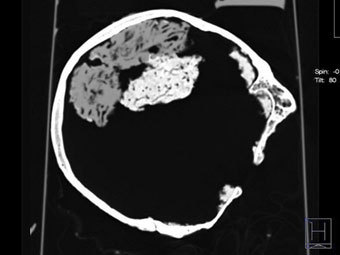

Сканирование найденного в Йорке черепа. Фото ©AFP

В Университете Йорка на севере Англии в ходе земляных работ был обнаружен череп, внутри которого сохранился мозг, передает в пятницу агентство Associated Press.

По мнению ученых, черепу более 2000 лет, что делает его древнейшей находкой такого рода на территории Великобритании и одной из древнейших в мире. Мозг достаточно хорошо сохранился, хотя пока нельзя сказать, обнаружен ли весь орган или только его часть.

Пока не выдвинута основная версия, почему голову древнего человека захоронили отдельно от тела. Среди предположений - ритуальное погребение и жертвоприношение. По мнению экспертов, едва ли исследование найденного мозга принесет открытия в области неврологии, однако с точки зрения археологии этот череп весьма привлекателен.